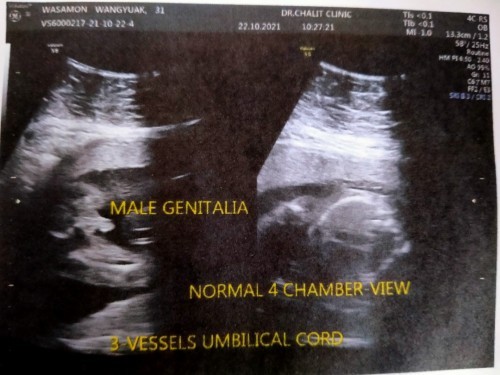

ซาวด์ตอน 20 วีคค่ะ คุณหมอบอกแบบไม่ลังเลเลย ว่าคุณแม่ได้ลูกชาย🤣🤣 ตอนนี้ 26+1 จ้า